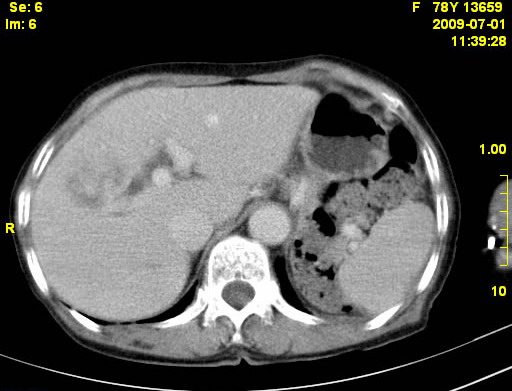

以下是引用zjzjr在2009-7-3 11:02:00的发言:[br]动脉期不均匀强化,门脉期及延迟期强化明显,肝门部见肿大淋巴结影,肝内胆管扩张.考虑肝右叶前段胆管细胞癌伴肝门淋巴结转移,胆内胆管扩张.慢性胆囊炎.

以下是引用dsl555在2009-7-4 10:59:00的发言:[br]考虑肝右叶前段胆管细胞癌伴肝门淋巴结转移,胆内胆管扩张.慢性胆囊炎. [br][br]支持。